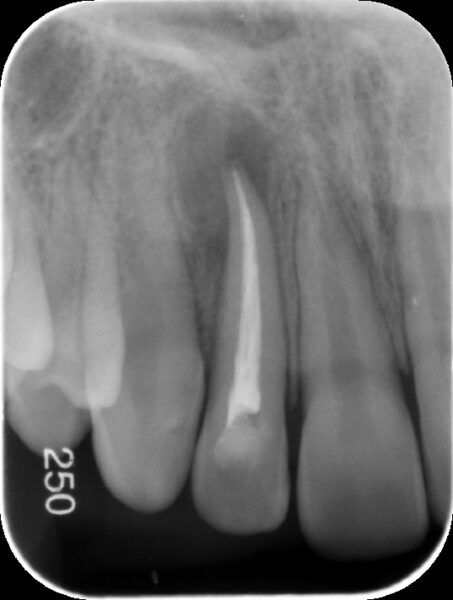

【術直後のレントゲンと口腔内写真】

上記で確認した根の先端まで緊密に根管充填材が到達していることが確認されます。